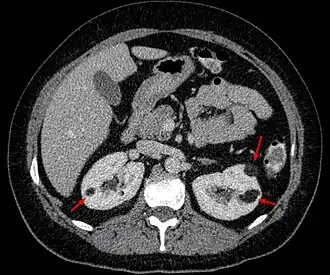

![]() Angiomiolipomas en ambos riñones (flechas) en una tomografía axial computarizada. | ||

Es un tumor benigno poco habitual; es el doble de frecuente en mujeres que en hombres. Se suele diagnosticar en adultos jóvenes de forma casual, en un estudio de imagen realizado por otro motivo en el 80% de los casos. Menos frecuentemente (15%) se diagnostica a raíz de una complicación hemorrágica denominada Síndrome de Wünderlich. Se suele detectar con ecografía, como una masa renal de aspecto hiperecogénico (debido a su contenido graso) pero el diagnóstico definitivo (para diferenciarlo de un tumor maligno) se establece con TAC con contraste radiológico o Resonancia Magnética sin contraste. No está indicada la biopsia por el riesgo de sangrado (al tener en su composición tejido vascular). Una vez establecido el diagnóstico de angiomiolipoma, el seguimiento se puede realizar con ecografía sin necesidad de otras pruebas de imagen. Se puede presentar de forma aislada, pero hay casos asociados a la esclerosis tuberosa o a la linfangioleiomiomatosis en cuyo caso los angiomiolipomas están presentes en ambos riñones.